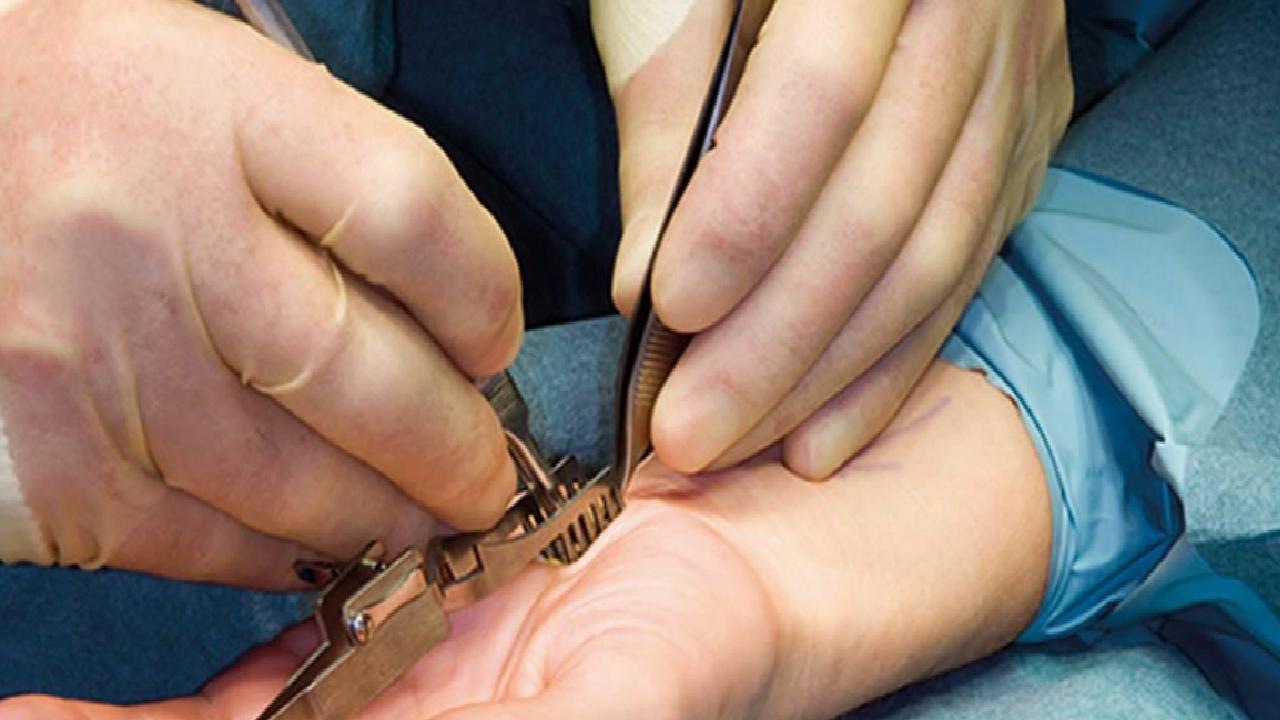

İlaç ve diğer alternatif tedavilere rağmen ağrı ve kuvvetsizlik şikayetleri devam eden veya ilerlemiş hastalar için basit ve lokal anestezi altında yaklaşık 15 dakika süren ufak bir operasyon ile tam iyileşme elde etmek mümkün. İki haftalık el istirahat sonrası hastalar normal günlük yaşantılarına uyum sağlayabilirler.